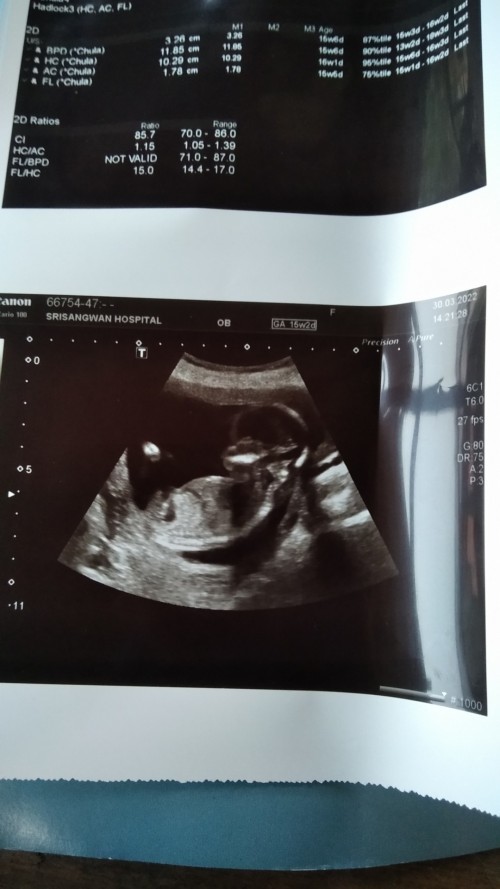

15w+2ค้ะ

Post reply image